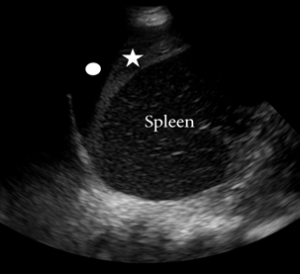

Perisplenic [left upper quadrant (LUQ)] view:

• To obtain the perisplenic or LUQ view in the E-FAST exam, the probe is positioned to detect free intraperitoneal fluid and assess for hemothorax.

• Since the left kidney lies slightly more posterior and higher than the right kidney, the probe should be placed in the posterior axillary line typically between the 9th and 10th intercostal spaces with the orientation marker pointed cephalad.

• The left upper quadrant view mirrors the right: the spleen appears at the top of the ultrasound monitor, the kidney to the right and the diaphragm to the left. In trauma, fluid tends to accumulate around the spleen especially in the subphrenic space rather than between the spleen and kidney.

• The presence of fluid in this region usually suggests splenic injury. To evaluate for a hemothorax, look above the diaphragm for any hypoechoic fluid collection and check for the abnormal continuation of the spinous line into the thoracic cavity, a finding known as the spine sign which confirms the presence of fluid allowing posterior acoustic transmission into the chest.

Figure: Positive E-FAST LUQ